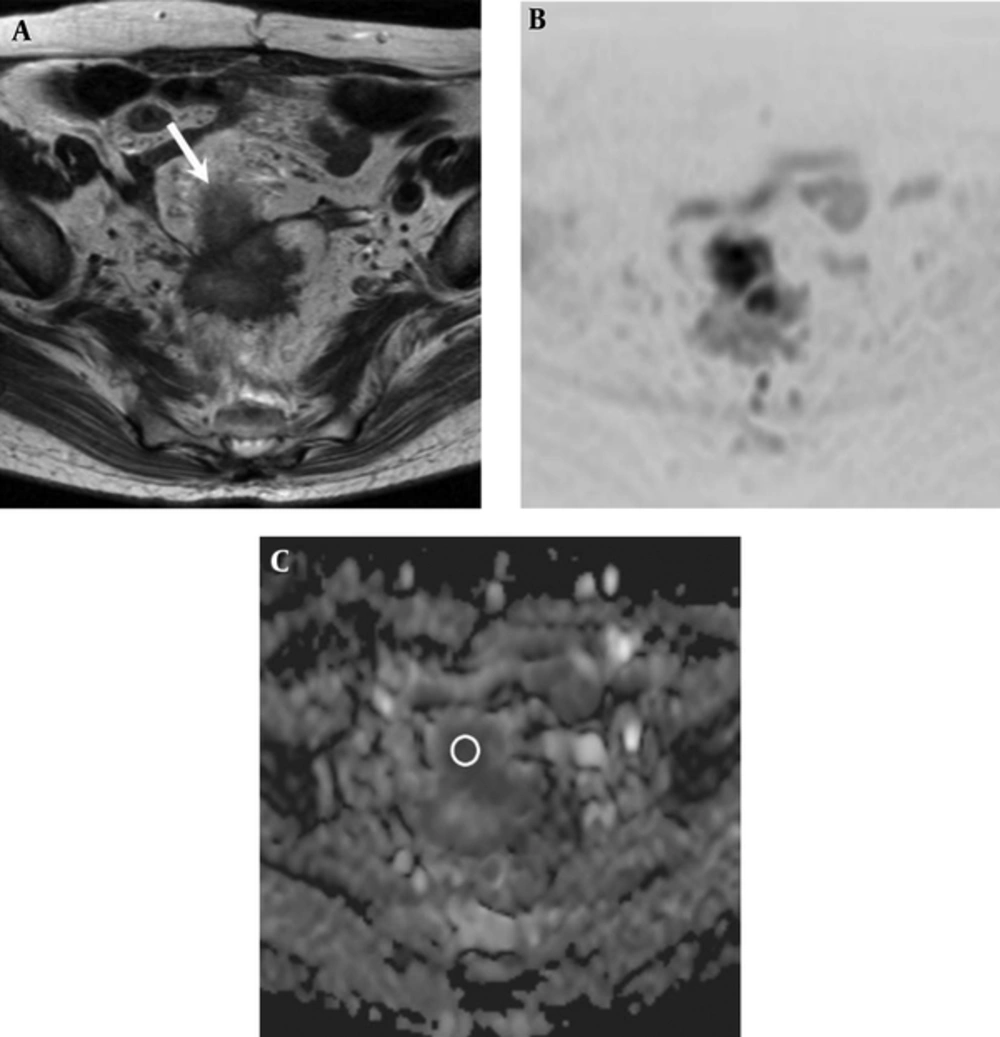

Two experienced radiologists with 6 and 5 years of post-training experience interpreting MR images, who had no knowledge of patient clinical information, measured the ADC value of rectal cancer in consensus. For the ADC value measurement, mean ADC value was obtained by placing a circular region-of-interest (ROI) cursor (37 - 837 mm2). A ROI was drawn to encompass the entire tumor at the image presenting the largest cross-section area of the tumor (Figure 1).

A 74-year-old woman with rectal adenocarcinoma who was diagnosed with lung metastasis 6 months after surgery. A, Axial T2-weighted image shows an ill-defined mass located in the rectosigmoid portion (white arrow). B, Diffusion-weighted image (reversed black-and-white image) and C, Apparent diffusion coefficient (ADC) map show a low ADC value (0.721 × 10-3 mm2/sec) in the mass (circle in part C).